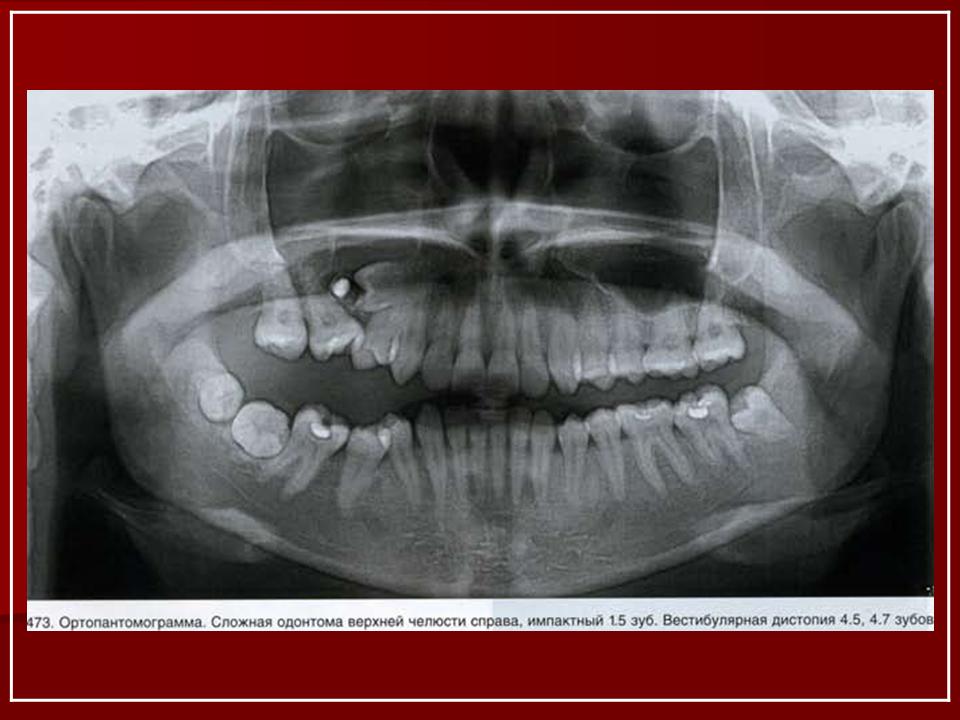

Одонтома - опухоль, образующаяся в результате порока развития и формирования зубных тканей. Одонтомы разделяются на простые и сложные. Простая одонтома связана с пороком развития одного зубного зачатка. Сложная одонтома связана с нарушением развития нескольких зачатков зубов, поэтому содержит твердые ткани на разных стадиях развития. В редких случаях одонтома имеет вид кисты, содержащей почти сформированные зубы. При гистологическом исследовании опухоли обнаруживают различные ткани: эмаль, дентин, цемент, пульпу, фиброзную ткань, кость. В мягких (кистоподобных) одонтомах в стенках содержатся зачатки элементов зубного эпителия. Одонтомы чаще встречаются в молодом возрасте. Растут медленно. Локализуются в основном в нижней челюсти. Рентгенологическая диагностика одонтом не представляет особых трудностей. На фоне обычной костной ткани выявляется очень плотное, округлой формы образование, окруженное ободком просветления (за счет фиброзной капсулы). В зубном ряду, как правило, отсутствует один или несколько зубов.

Одонтома